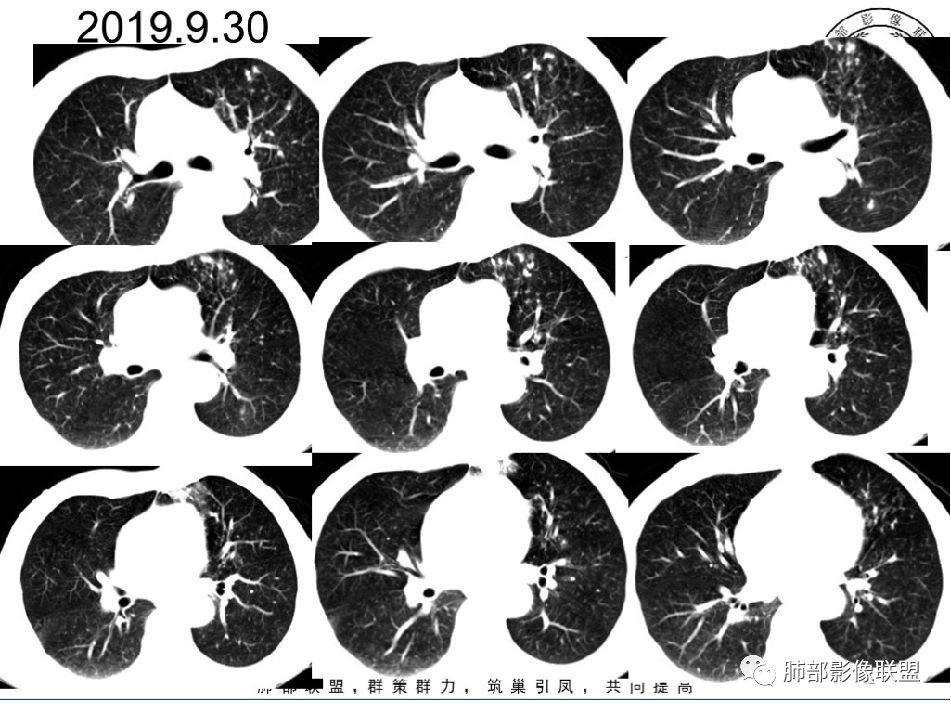

2019--9-30复查CT:与2019-8-12比较,左下肺后外基底段较前吸收减少。(有效)但前内基底段病灶较前增多,原空洞无变化,其下方病灶内新发空洞与原空洞相连,10.5*6.4mm,(小空洞),(无效?)。

2019-10-8:支气管镜通畅。支气管炎症。左上叶尖后段活检。IgE1140IU/ml,CPR14.1ml

GLU-2 8.56mmol/L,HbA1C:6.2%。